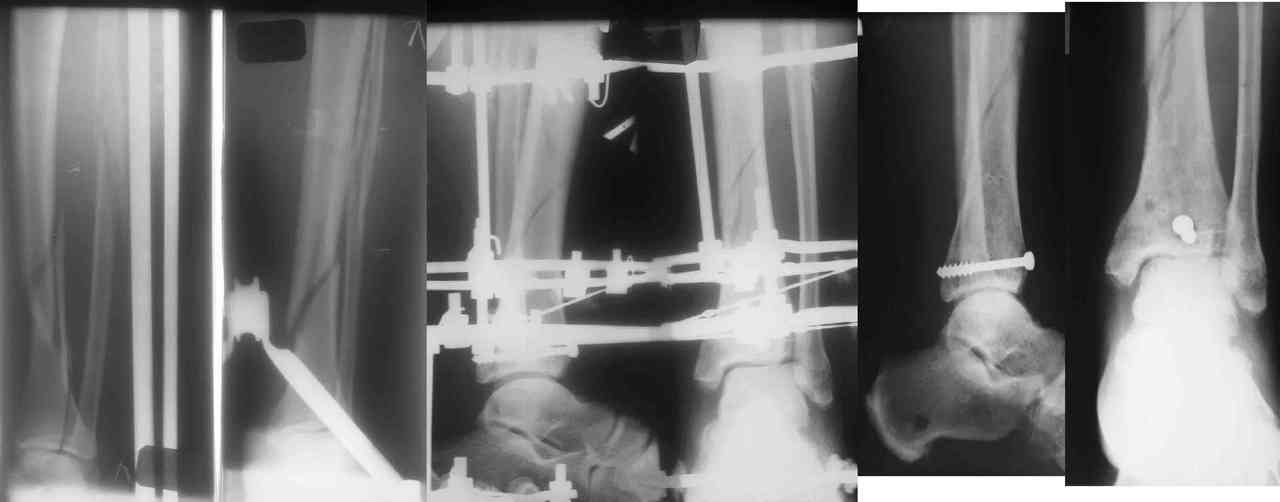

Пример -

задний край и диафиз

По поводу конкретного вопрошаемого случая:

1. Скорее всего в аппарате удасться вывести закрыто всё, кроме внутренней лодыжки. Открывайтесь и фиксируйте либо спицей с упором,

либо винтом.

2. ЭОП - очень спорное достижение в таких случаях. Сильные искажения.

Буквально вчера переделывали практически похожий случай. На ЭОПе всё идеально. На пленке - ступенька переднего края. Брали повторно, но уже

пригласили рентгенлаборантку в операционую сделать снимок.

3. Последнее время всё чаще делаем аппарат Илизарова в симбиозе с винтами, которыми фиксируем края (передний и задний), лодыжки и теперь - диафиз.

Позволяет пораньше снять аппарат.